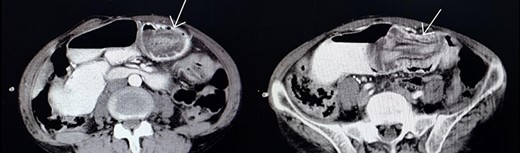

Gastroenterologist reported a 400 cc bloody-biliary discharge in the gastric cavity. A protruded edematous jejunal mucosa which formed a mass-like lesion was also evident. No sign of gangrene or ulceration was reported. In the next step, we requested an abdominopelvic CT scan (Fig. 2) which also showed target sign in favor of intussusception of jejunum. After initial resuscitation, emergency laparotomy was undertaken and in exploration, a distal jejunum loop about 10 cm long, invaginated to the gastric cavity with no sign of ulceration or necrosis was found. The jejunal loop had no pathological causes (leading point) and was reduced without a need for resection. The abdominal cavity was explored entirely, there were no free abdominal fluid or any pathologic finding. Postoperative follow-up was uneventful. The patient discharged 6 days later.

Jejunogastric intussusception showed (arrow) in abdominopelvic CT scan with Iv/oral contrast.